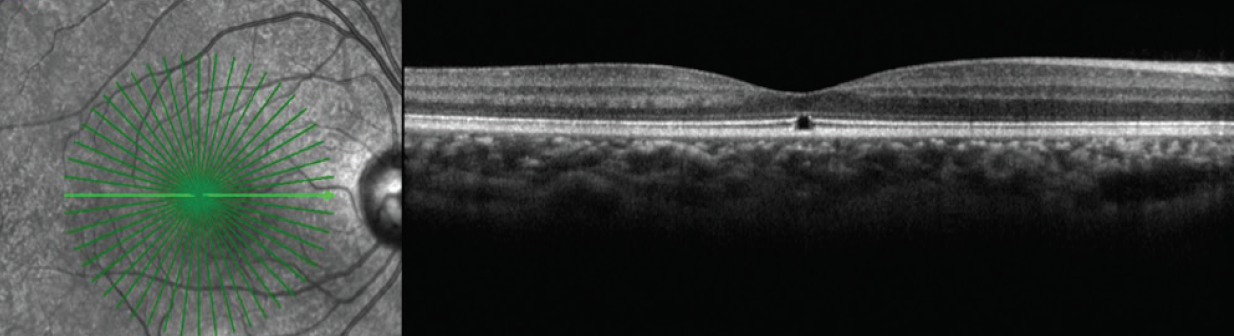

Figure 1. OCT of the patient’s right (A) and left (B) eyes 3 years prior to presentation. The presence of focal subfoveal ellipsoid defects led to a diagnosis of solar retinopathy at that time.

Baseline visual acuity before this presentation was 20/25 in each eye (OU). At this visit, her visual acuity OS had decreased to 20/400. Anterior segment examination was notable for an absence of inflammation. Funduscopic exam OD revealed focal hypopigmentation at the fovea (Figure 2A), and spectral-domain optical coherence tomography (OCT) demonstrated a focal defect involving the outer retina and ellipsoid layer, which was stable from 3 years prior (Figure 3). Fundoscopic exam OS was notable for absence of any posterior segment inflammation and a circumscribed central granular yellow lesion (Figure 2B). OCT revealed disruption of the subfoveal ellipsoid layer, hyperreflective debris involving the outer retina and apical surface of the retinal pigment epithelium (RPE), and a thickened choroid OS (Figure 4). Fluorescein angiography (FA) OS demonstrated early central hypofluorescence and parafoveal patchy hyperfluorescence without leakage (Figure 5). Electroretinography (ERG) demonstrated normal amplitudes OD and reduction of macular sensitivity OS.